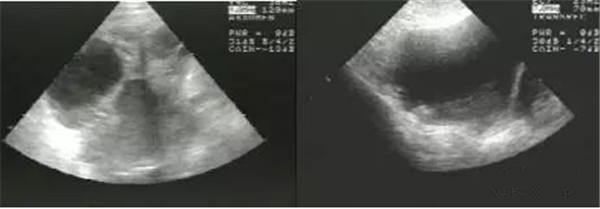

2、宫腔积血、积脓、积液

(宫腔积液)